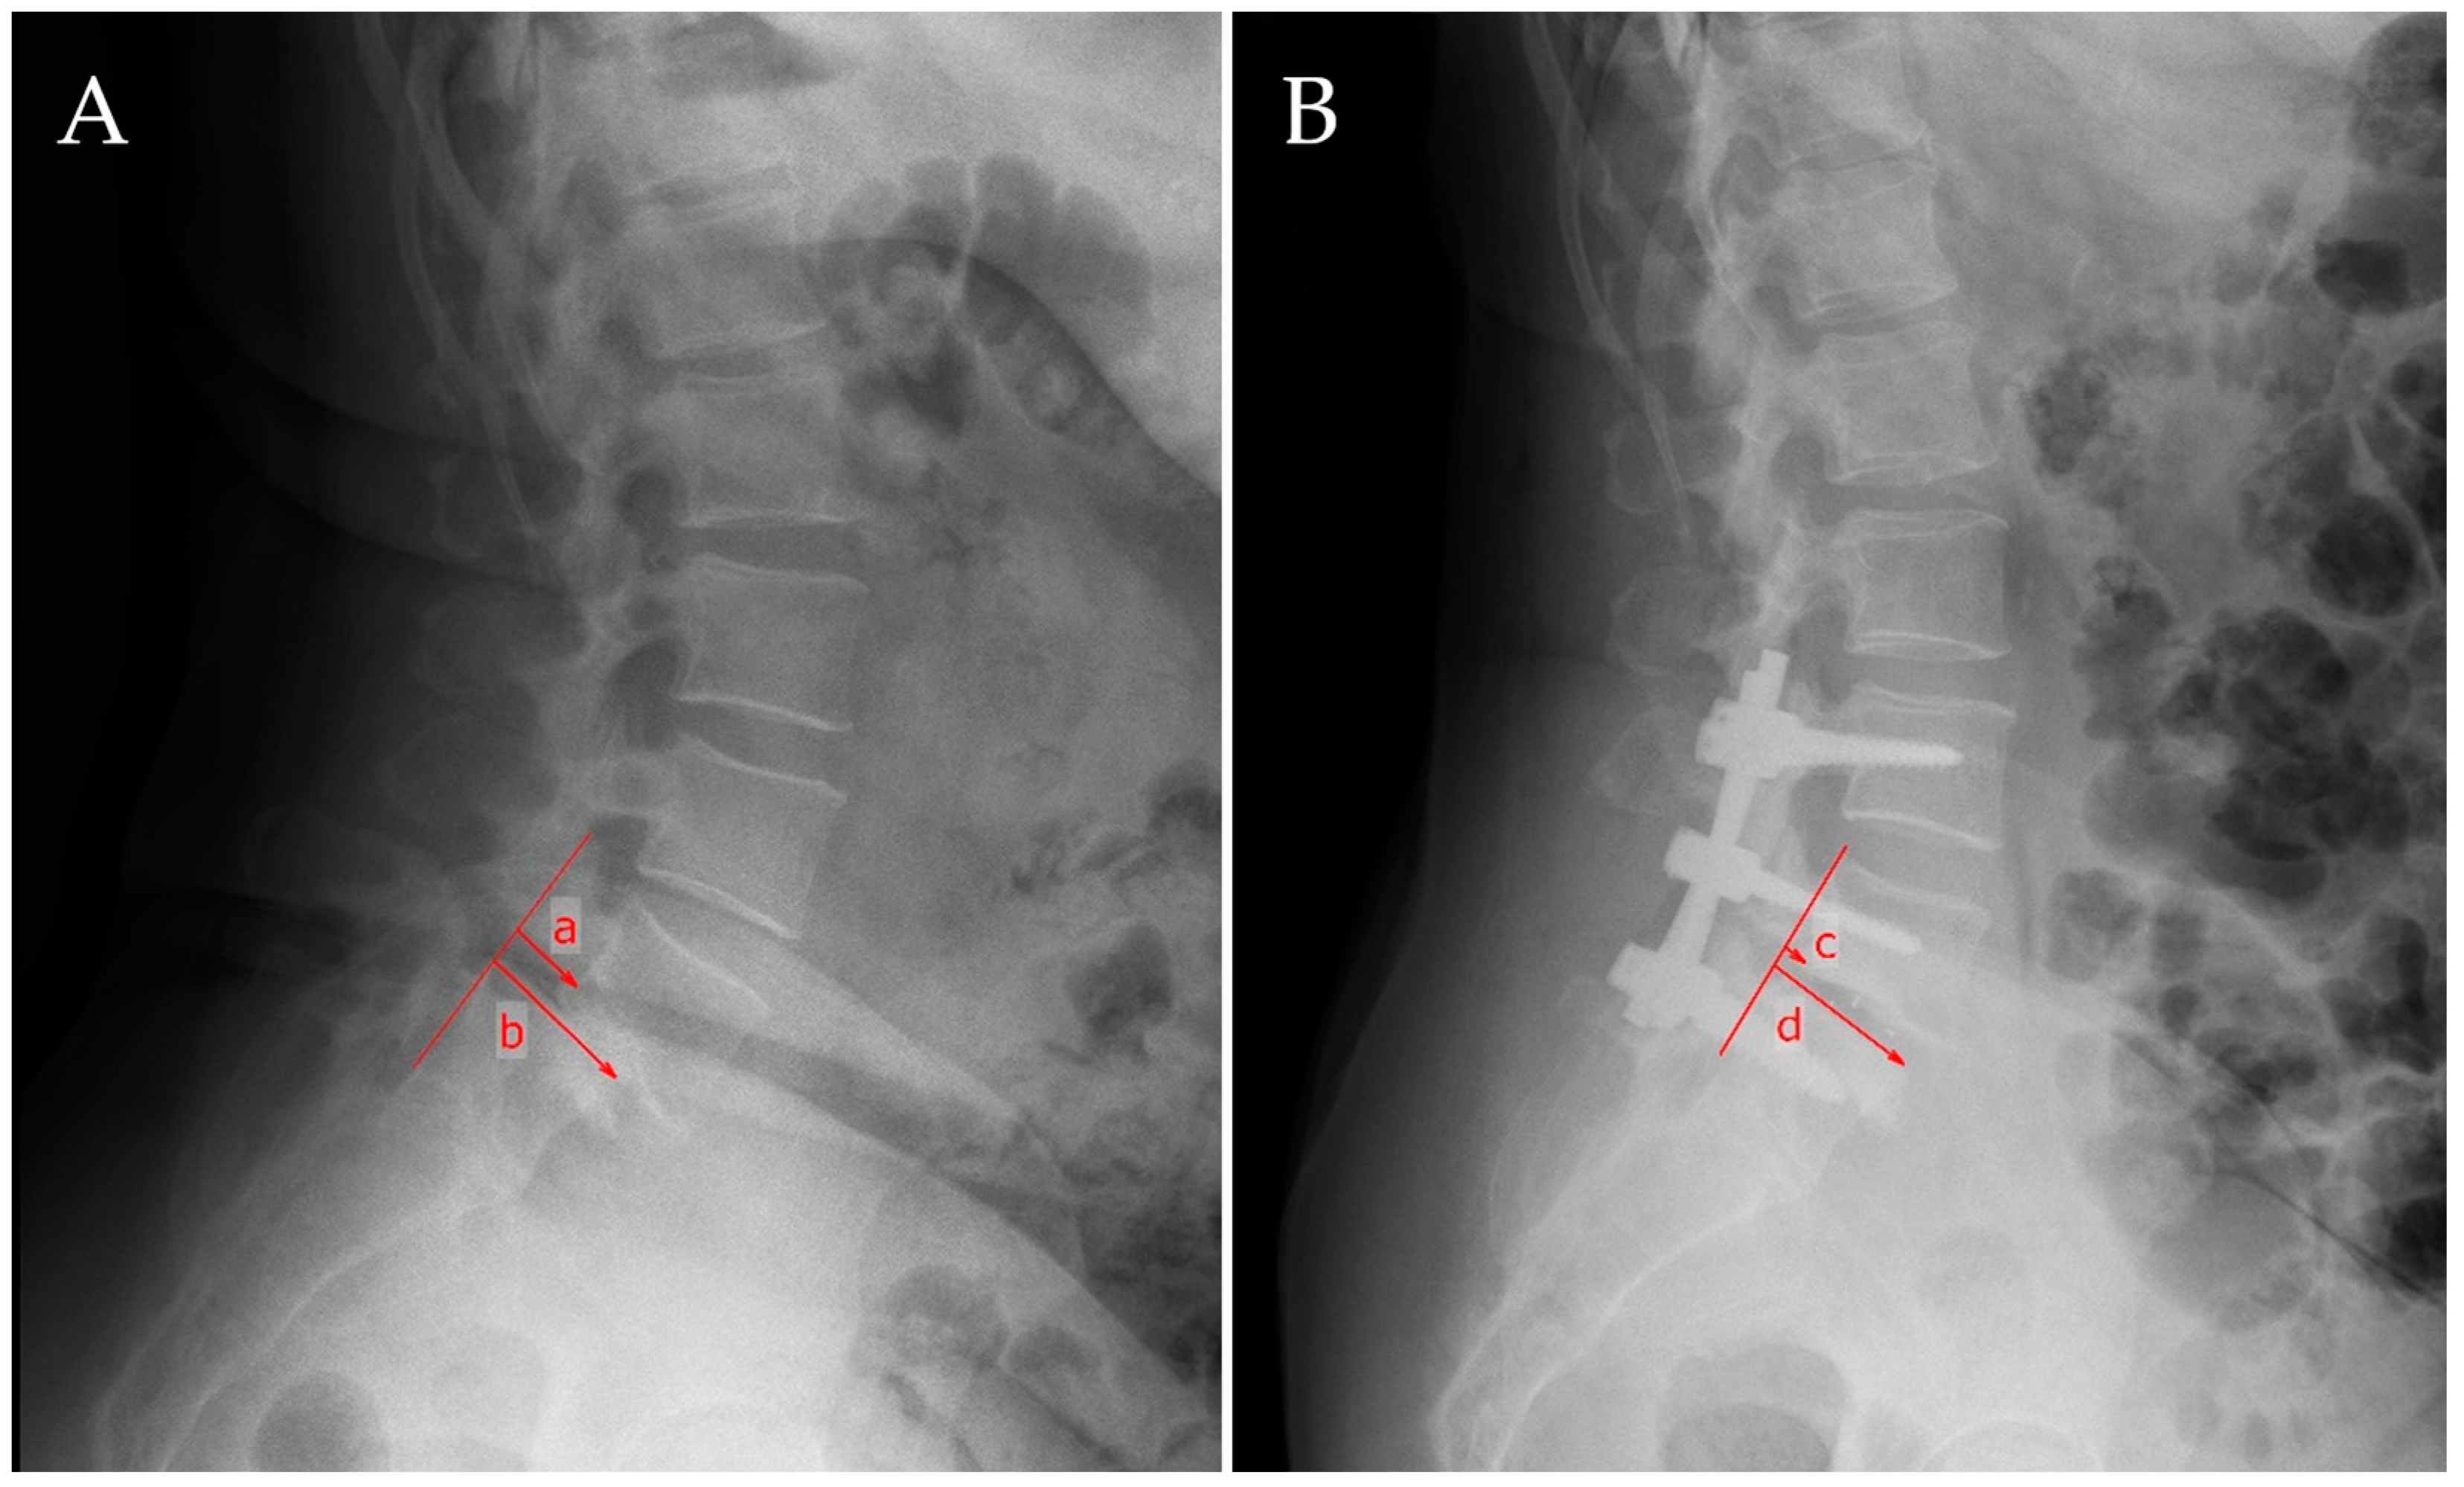

For the assessment of spondylolisthesis, we performed several measurements as depicted in Figure 1: On the lateral projection, a line was drawn alongside the posterior wall of the two adjacent vertebral bodies that constituted the slippage, allowing for the evaluation of vertebral translation, and a measurement in centimeters of the actual slippage was performed. Measurements were assessed pre- and postoperatively.

Figure 1. Measurement of pre-and postoperative spondylolisthesis slippage. A vertical line was drawn through the posterior margin of the caudal vertebra. On preoperative assessment (A), a is the distance from this vertical line to the posterior margin of the upper vertebra, while b is the length of the cranial endplate of the caudal vertebra, c is the distance from the line drawn vertically through the posterior margin of the vertebra below to the posterior wall of the upper vertebra, and d is the length of the superior endplate of the below vertebra assessed postoperatively (B). The preoperative slippage is defined as a/b, whereas the postoperative slippage is defined as c/d.